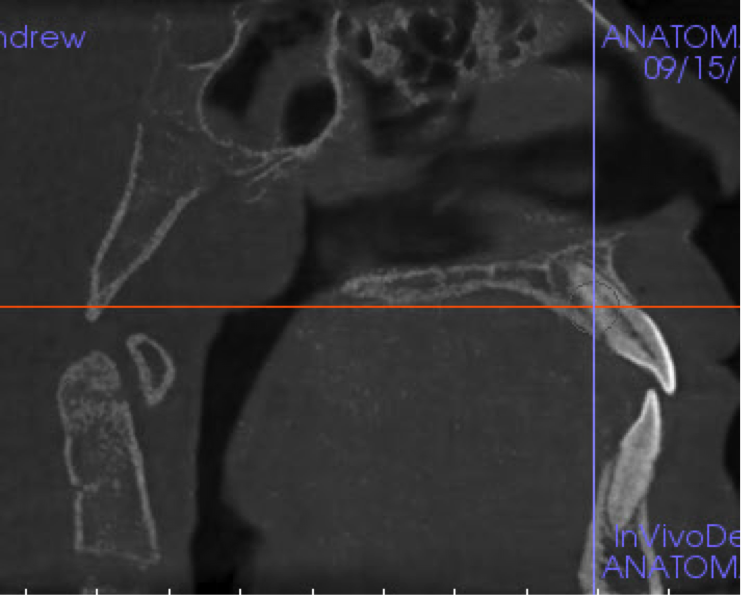

Other kinds of artifacts that are related to the CBCT technology itself may be present and compromise image quality, sometimes rather significantly.7 These artifacts are an inherent problem of CBCT and medical computed tomography because their appearance is a product of the reconstruction algorithms employed to compose the digital CBCT and CT images. In addition, the presence of any radiopaque materials is a frequent cause of artifacts. Metallic dental restorations, fixed prostheses, posts, and even gutta-percha may create artifacts that can obscure the visualization of the region of interest (Figure 3). As a result, fine diagnostic tasks may be impossible in proximity to restorations with high radiopacity. A number of CBCT manufacturers currently offer artifact reduction applications. These seem to have improved the resulting image quality; however, any possible gain in diagnostic efficiency has yet to be determined (Figure 4).

(4.) When compared to the original CBCT image (left), the application of artifact reduc- tion algorithms have improved the visualization between the two dental implants (right image).

Figure 4